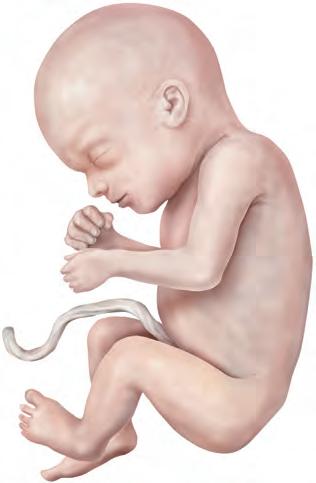

9a-12a settimana A causa del rapido accrescimento dimensionale, entro la fine della 12a settimana la LVC raddoppia. In rapporto al tronco, il collo e gli arti, in particolare quelli superiori, aumentano (A). La faccia assume tratti maggiormente caratteristici, poiché gli occhi, inizialmente collocati su un piano piuttosto laterale, migrano in direzione ventrale e gli orecchi assumono la loro posizione definitiva ai lati della testa. Le palpebre aderiscono le une alle altre, chiudendo la rima palpebrale. Entro l’11a-12a settimana, le anse intestinali collocate nel cordone ombelicale si riportano nella cavità addominale ora più spaziosa. Nella 12a settimana ha luogo il definitivo differenziamento tra organi genitali esterni maschili e femminili.

13a-16a settimana Tale periodo è caratterizzato da un accrescimento estremamente rapido del tronco, del collo e degli arti. La testa si solleva. Il corpo si copre di sottili peli, la lanugine, e il tipo di capigliatura diventa riconoscibile. L’ossificazione procede, cosicché nel feto di 16 settimane (B) le ossa sono riconoscibili in radiografia.

17 a-20 a settimana L’accrescimento del feto rallenta nuovamente e durante tale periodo l’aumento di peso è scarso. Anche i segmenti degli arti inferiori hanno raggiunto le loro proporzioni definitive (C). Le ghiandole sebacee secernono una sostanza grassa e biancastra, la vernice caseosa, che protegge la cute del feto dalla macerazione causata dal liquido amniotico. Si sviluppano i capelli e le sopracciglia. In tale periodo la madre percepisce per la prima volta i movimento del feto ed è consigliabile effettuare un esame ecografico di routine (D).

21a-25a settimana L’aumento di peso continua. Tuttavia, poiché i cuscinetti adiposi sottocutanei non si sono ancora formati e la cute si ac-

cresce rapidamente, il feto presenta un aspetto rosso e grinzoso. Si sono sviluppate le unghie, la faccia e il corpo hanno assunto l’aspetto di un feto al termine di gravidanza. Tuttavia, di regola soltanto i feti partoriti dopo la 25a settimana riescono a sopravvivere, poiché solo a partire da questo momento il sistema respiratorio è sufficientemente sviluppato per iniziare la sua attività funzionale.

26a-29a settimana In seguito allo sviluppo dei cuscinetti adiposi sottocutanei, il corpo diventa più rotondo e robusto e aumenta notevolmente di peso. Le palpebre si separano, cosicché gli occhi sono nuovamente aperti (D). Le sopracciglia e le ciglia sono ben sviluppate. I capelli si allungano. In linea di principio, a partire da questo periodo i feti partoriti prematuri sono capaci di sopravvivere.

30 a-34 a settimana L a percentuale di tessuto adiposo sottocutaneo aumenta ulteriormente rispetto al peso corporeo; anche gli arti superiori e inferiori si irrobustiscono e la pelle assume un colore roseo. Le unghie della mano si sono accresciute fino alla punta delle dita, mentre quelle dei piedi iniziano appena a formarsi. Nei feti di sesso maschile i testicoli iniziano a discendere (discesa dei testicoli).

35a-38a settimana Nell’ultimo mese di gravidanza, soprattutto il tronco del feto aumenta di larghezza. In corrispondenza della parete addominale, il punto di inserzione del cordone ombelicale è migrato al centro. Le unghie delle dita dei piedi raggiungono l’estremità delle dita e i peli della lanugine cadono, cosicché la cute è rivestita solamente dalla vernice caseosa. Nel feto di sesso maschile, i testicoli migrano nello scroto, mentre nel feto di sesso femminile le ovaie sono ancora collocate al di sopra della piccola pelvi.

Feto, 9a settimana Figura 8.12 Periodo fetale